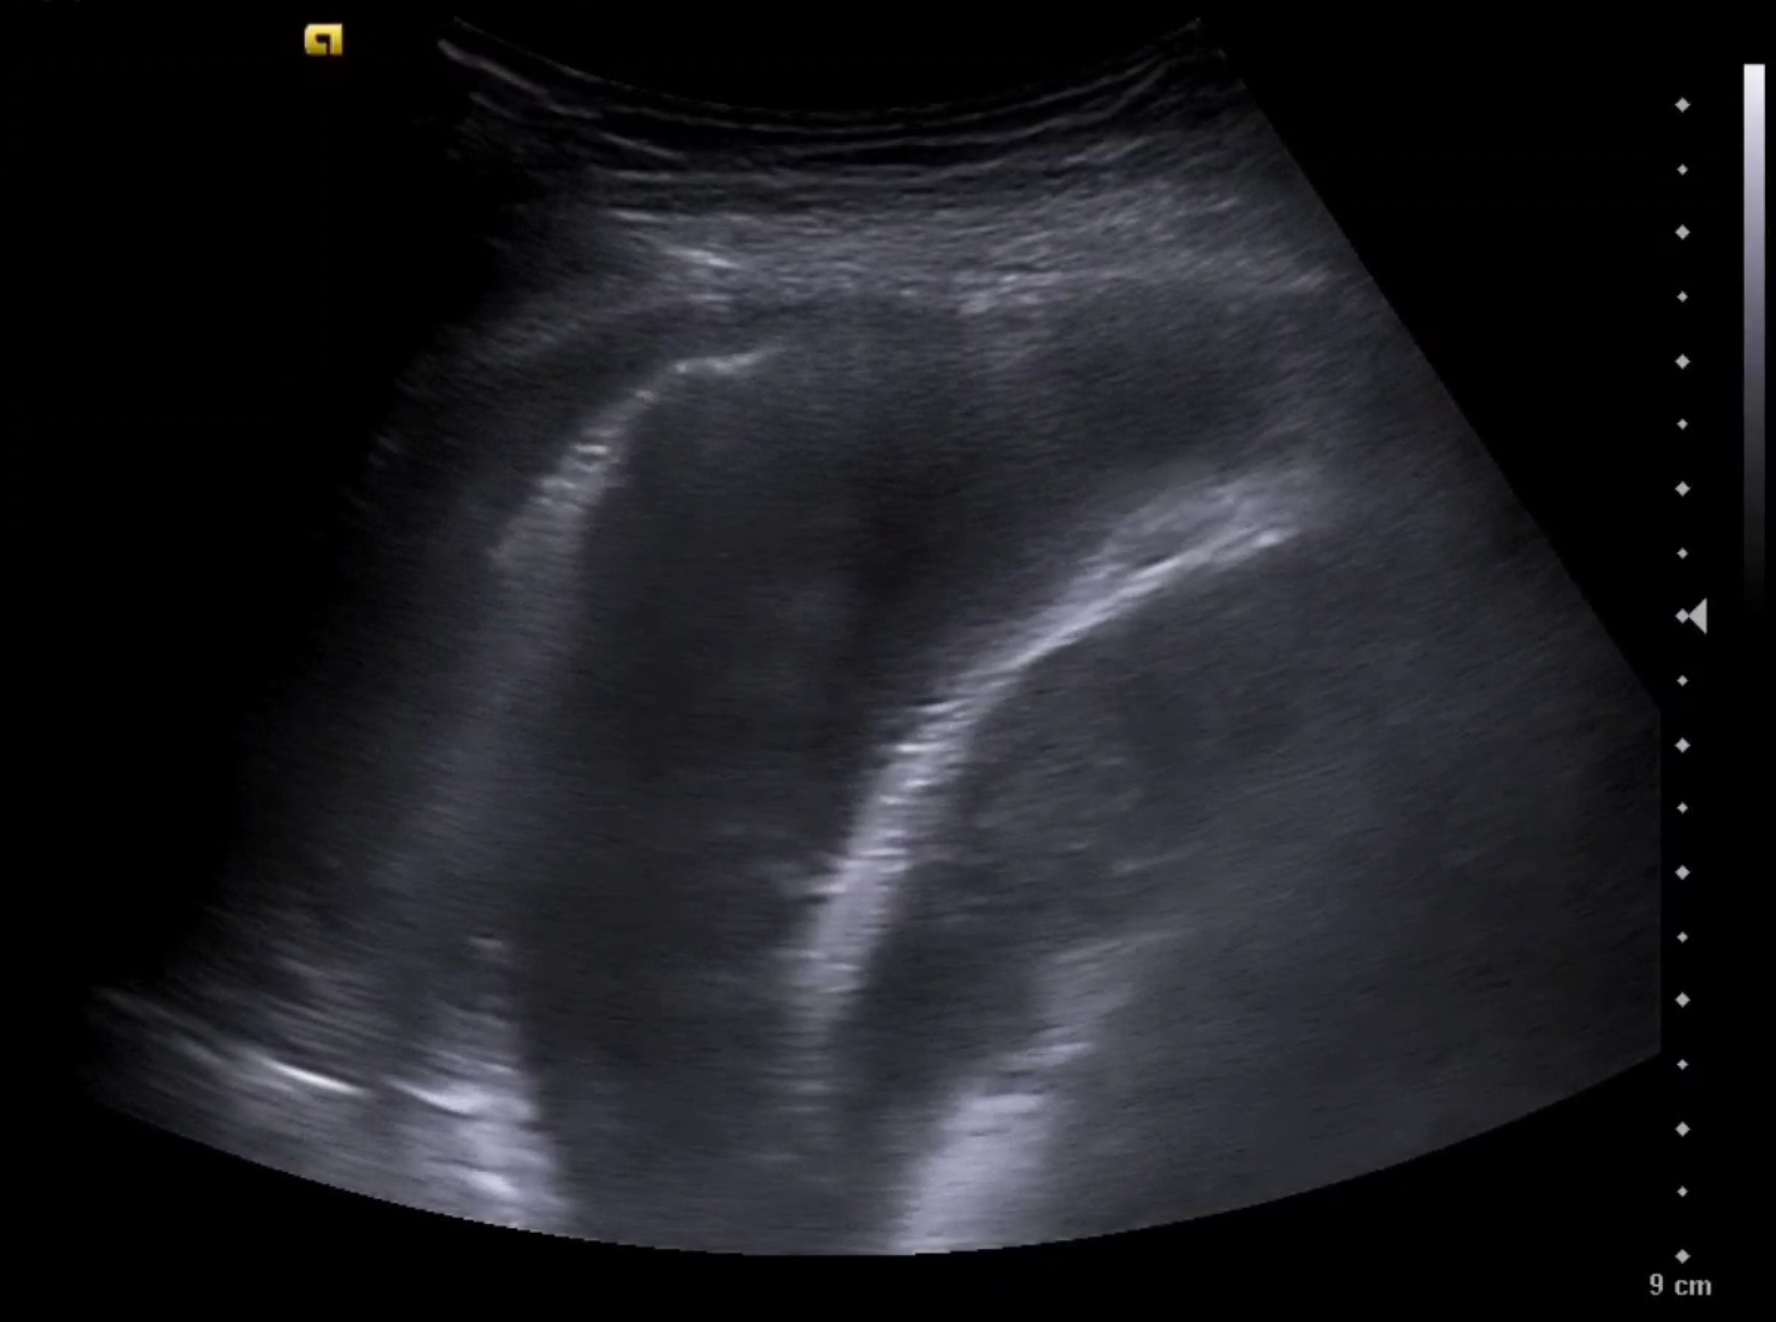

A las técnicas ya presentes en consulta como la ecografía abdominal a nivel de vena cava inferior (VCI) y ecografía pulmonar, se incorpora la ecocardioscopia y el protocolo VEXUS.

La sobrecarga de presión o volumen en un paciente provoca congestión intersticial, Nefrología aplica el protocolo VEXUS «Venous EXcess UltraSounds» tanto en el diagnóstico como en el seguimiento de múltiples patologías. Se han descrito 4 perfiles de congestión.

La ecografía complementa otras pruebas complementarias clásicas como: ECG, Rx Tórax y analítica (hierro, TSH, ProBNP y CEA125). Ya incorporadas, la ecografía abdominal para la VCI, la ecografía pulmonar y la ecocardioscopia, es el momento del protocolo VEXUS en el diagnóstico y seguimiemto de patologías como: Insuficiencia Cardíaca, s. CardioRenal o s. Nefrótico.